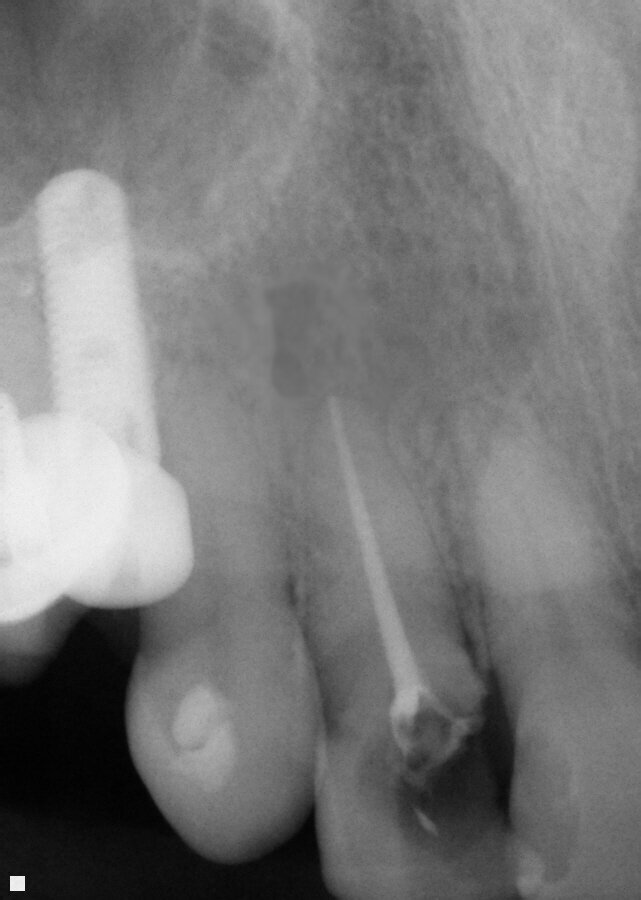

Fig. 14: Patient presented with complaint of pain on chewing on teeth 14 and 15 with increasing sensitivity to hot.

A 37-year-old male new patient presented with the complaint of pain with hot foods and beverages on teeth 14 (maxillary left first molar) and 15 (maxillary second molar) that had been increasing the past six months since he had restorations placed due to decay by the prior dentist before relocating to my area. A radiograph was taken, and slight apical widening was noted on both teeth (Fig. 14). Both teeth were responsive to testing with heat and cold that lingered for a minute or two after the stimulus was removed. Both teeth also tested to slight responsiveness to percussion stimuli. Patient was informed that based on what presented it was recommended that both teeth were moving toward needing endodontic treatment or we could adjust the occlusion and see if that helped with symptom improvement. The patient indicated due to the increasing sensitivity to hot foods and beverages he would prefer to initiate endodontic treatment at this time.